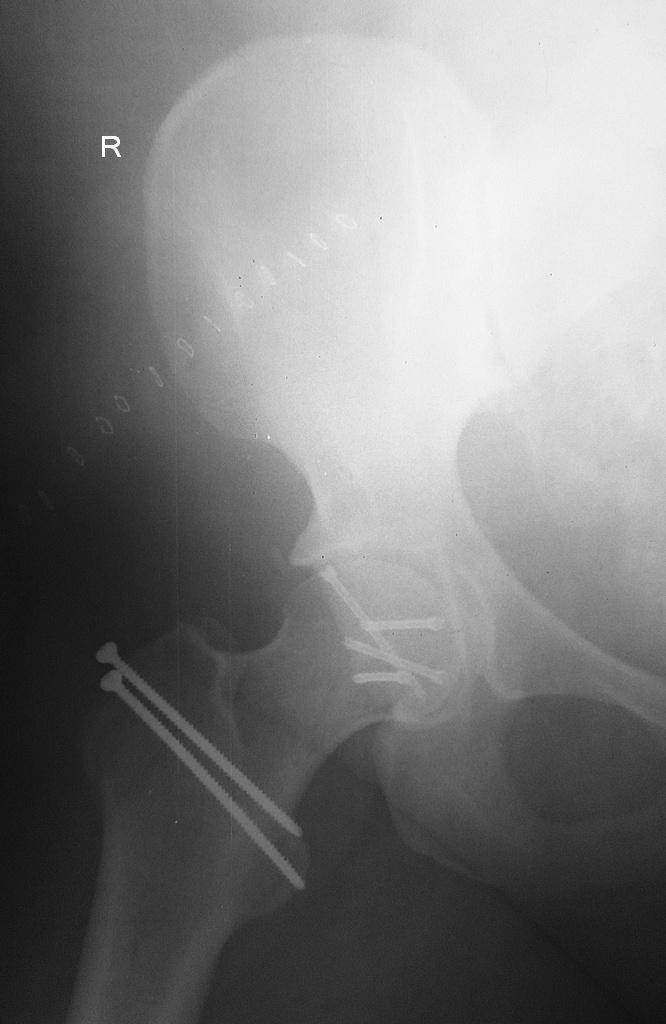

Привожу рентген снимки второй пациентки с Pipkin IV после операции.

Интраоперационных снимков, к сожалению нет. На 7 сутки после поступления

выполнили флип-остеотомию с передним вывихом головки бедра. Доступ

Kocher-Langenbeck.  Внутрисуставной фрагмент задней стенки вертлужной

впадины удалили, так он был фрагментирован и слишком малого размера.

Медиальный осколок головки оставался в полости сустава с целой круглой

связкой. Связку иссекли и после репозиции головку синтезировали винтами

Герберта.  Ушились с активным дренажем, так как пациентка с ожирением. В

принципе, пациентку можно присаживать на кровати.